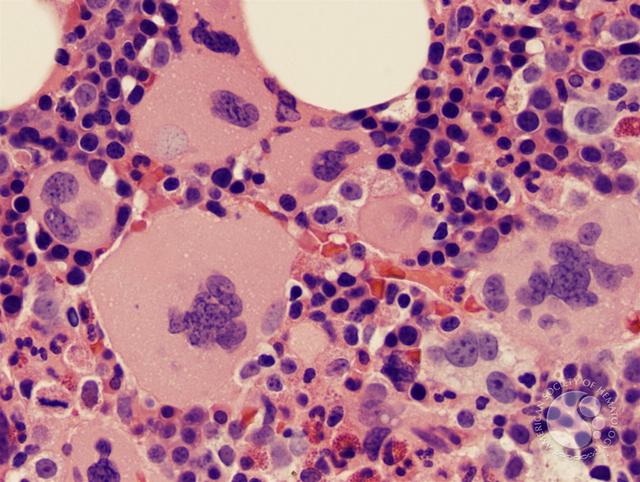

巨核细胞 图片来源:keyword-suggestions.com+ Z2 c0 m  |6 i9 ^) s